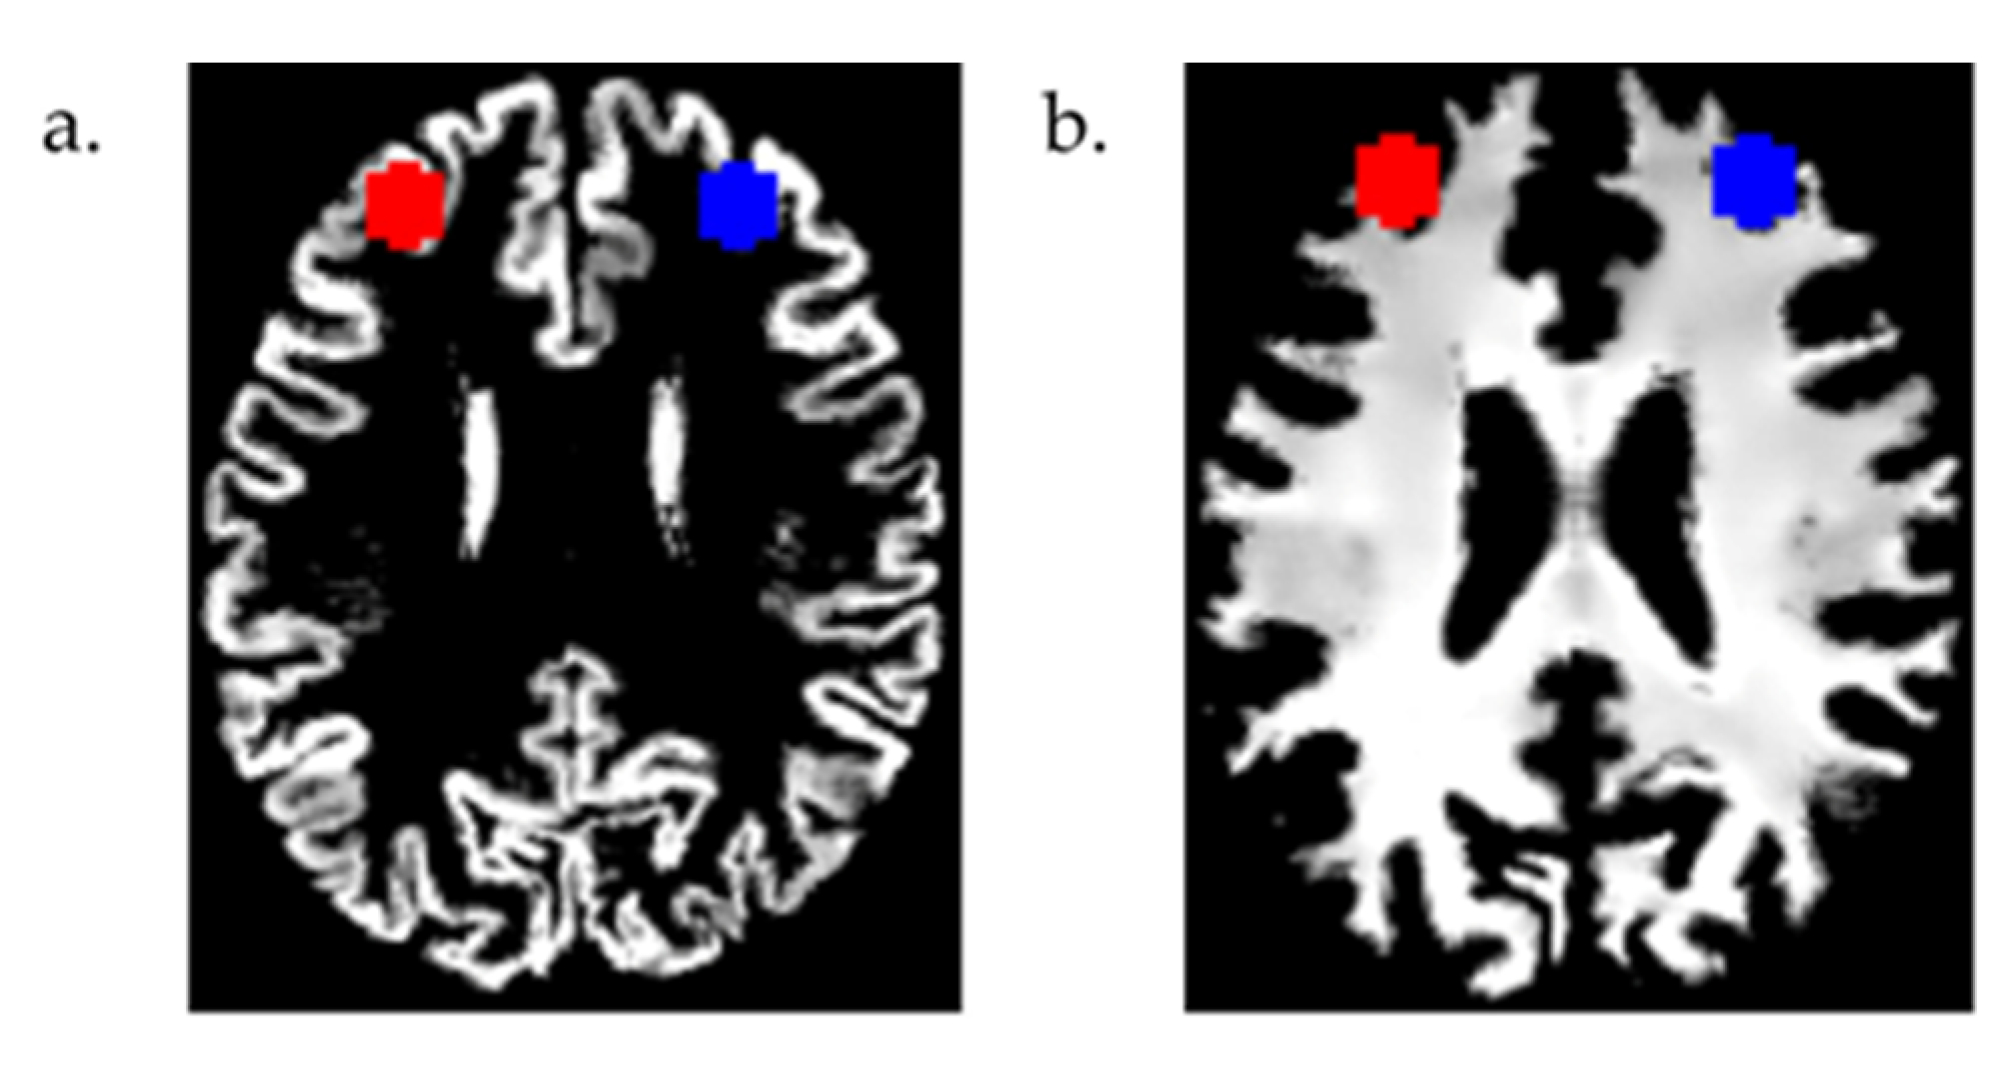

2.3. MRI Data Analysis

3.2. Region of Interest (ROI) Analyses

3.2.1. GM and WM Volume